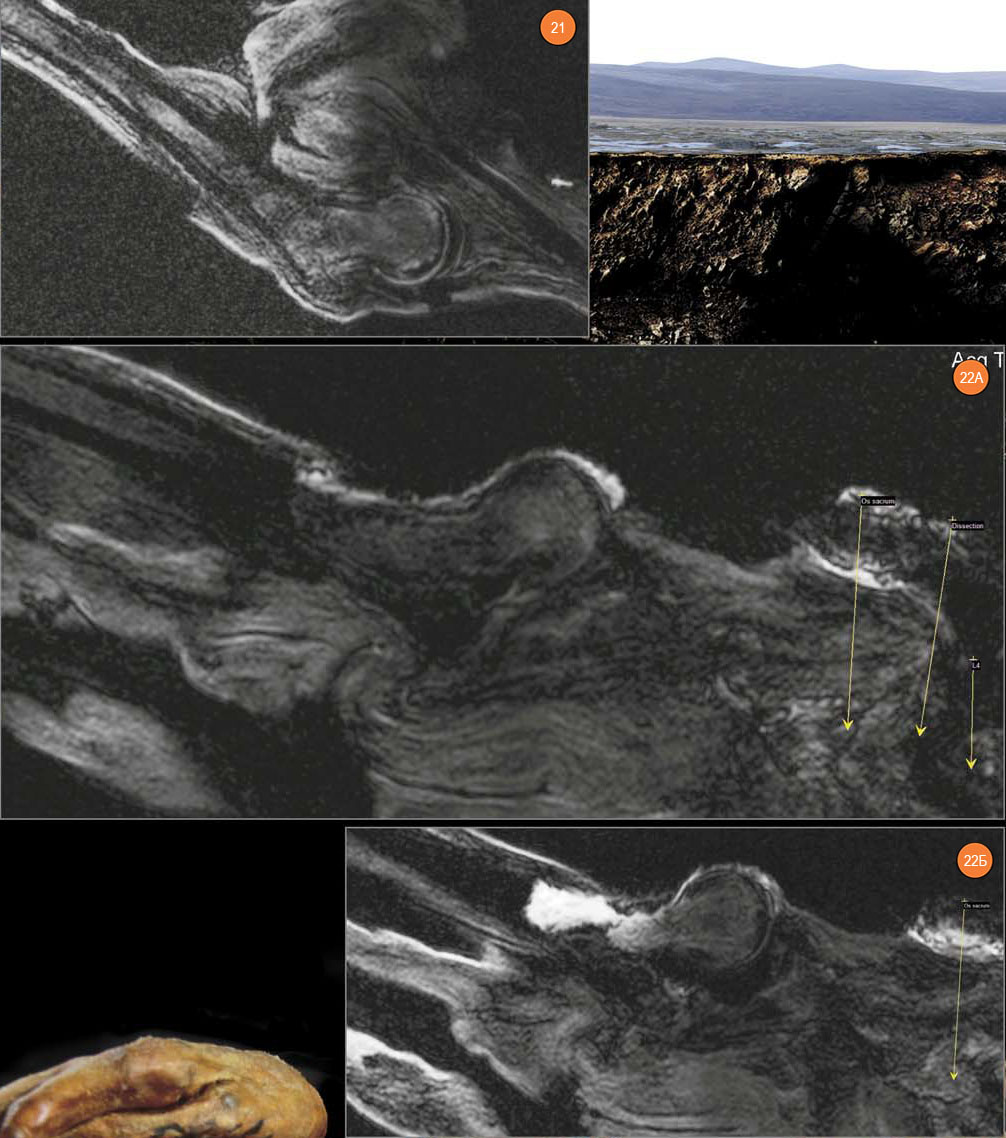

Визуализация правого тазобедренного сустава показала, что на момент исследования он был вывихнут: головка бедренной кости была выведена из гленоидальной ямки на 17 мм кпереди, а большой вертел из латерального положения переместился назад. На головке правой бедренной кости имеются субхондральные диффузные склеротические изменения глубиной до 5 мм. Угол шейки по отношению к телу бедренной кости составляет 129,2°.

Рис. 21. Левый тазобедренный сустав. Рис. 22. Правый тазобедренный сустав. А — имеется резкая отечность в области шейки и в межтрохантерной зоне (внутри сустава, видна «пустая» гленоидальная полость), Б — головка бедренной кости вывихнута за пределы края гленоидальной полости

Капсула этого сустава имеет явную отечность со скоплениями жидкости внутри суставной капсулы, с выраженной отечностью в прилежащей клетчатке правой паховой области. Именно эти данные позволяют утверждать, что изменения правого тазобедренного сустава носят прижизненный характер. В сочетании с травматической деформацией головки правой плечевой кости, деформацией передней крестообразной связки правого коленного сустава (о которой речь пойдет ниже) и деформации поясничного отдела позвоночника по типу сублистеза они дают основания предположить значительную прижизненную травму. Это могло произойти при падении с лошади.